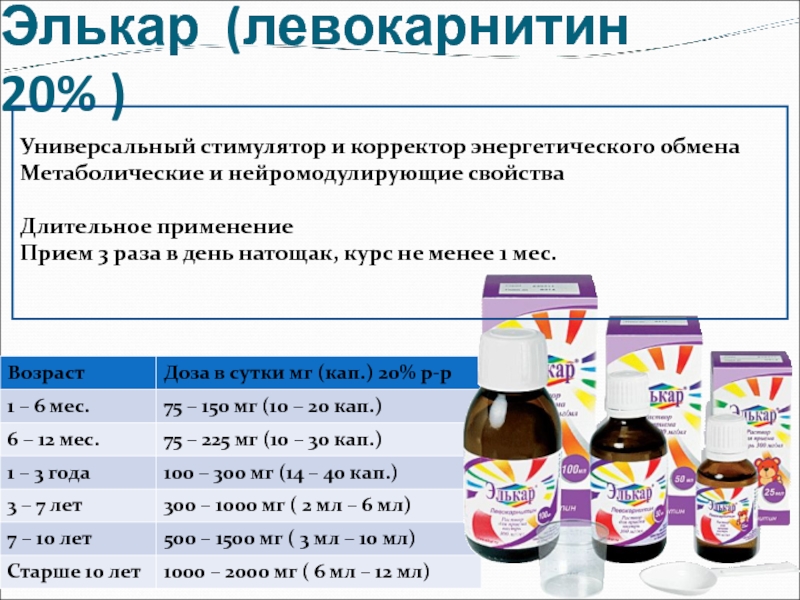

Приобретая Элькар в каплях, обратите внимание на инструкцию по приему, особенно, когда это касается детей. Элькар в каплях выпускается в виде 20% раствора и Элькар 30%

Инструкция по приему разная.

Элькар в каплях 20% чаще назначается новорожденным и детям до трехлетнего возраста, поскольку препарат этой концентрации легче дозировать. Детям с 3 лет и старше назначают Элькар 30%. Не перепутайте, Элькар 30% по инструкции назначается в гораздо меньшей дозировке, чем Элькар 20%.

Элькар 20% по инструкции для детей в возрасте до 1 года назначается по 10 капель 3 раза в день. Элькар 20% по инструкции для детей от 1 года до 6 лет назначается по 14 капель 3 раза в день. Возможно применение препарата в виде добавки к компоту или соку. Детям в возрасте от 6 до 12 лет препарат назначают по 1/4 чайной ложки 2 раза в день.

Элькар 30% по инструкции назначают детям от 3 до 6 лет по 5 капель 2-3 раза в день. Детям от 6 до 12 лет элькар 30% согласно инструкции назначают по 11-15 капель 2-3 раза в день.